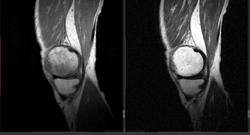

Мужчина 1963 г.р. Жалуется на боль в левом коленном суставе около 6 мес, в последний месяц стало совсем тяжко. Со слов заболел зимой, когда во время прогулки коленки сильно замерзли. Сам думаю на асептический некроз, но смущает множественность поражения.

Дмитрий, я в заболеваниях суставов не дока, но трабекулярный отек вкупе с выпотом может быть обусловлен воспалительными изменениями , но полностью начальные проявления аваскулярного некроза не могу отрицать.

я бы не поставил аваскулярный некроз. если исключена травма, дифференцировать с артритом.

Хрящ не поврежден, для артрита...